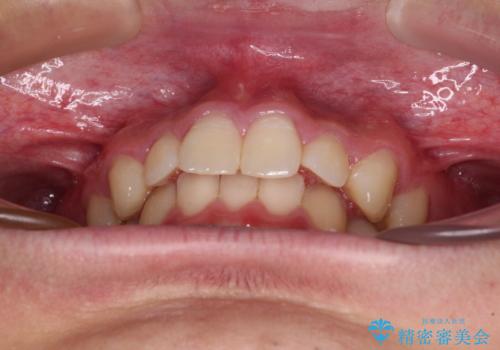

- 上下前歯のデコボコと深い咬み合わせを気にして来院された患者様です。

下顎前歯が一本欠損しており、下顎の歯列が小さいため、ディープバイトになりやすい状態でした。